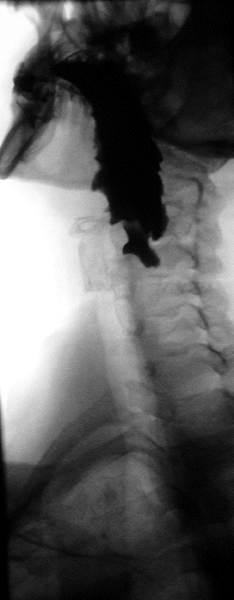

A barium swallow study is also known as a barium esophagram and needs little if any preparations for the study of the larynx, pharynx, and esophagus when studied alone.[11][12]

A thick barium mixture is swallowed in supine position and fluoroscopic images of the swallowing process are made. Then several swallows of a thin barium mixture are taken and the passage is recorded by fluoroscopy and standard radiographs. The procedure is repeated several times with the examination table tilted at various angles. A total of 350–450 mL of barium is swallowed during the process.[14][15] Normally, 90% of ingested fluid should have passed into the stomach after 15 seconds.[16]

Right anterior oblique (RAO) view is to see the oesophagus clearly, away from overlapping spine.[13] AP (anterior-posterior) view is also done to visualise the gastroesophageal junction.[13] AP and lateral views are also done to visualise the hypopharynx during swallowing at a frame rate of 3–4 per second. Left posterior oblique (LPO) position is used to identify hernias, mucosal rings, and varices.[13]